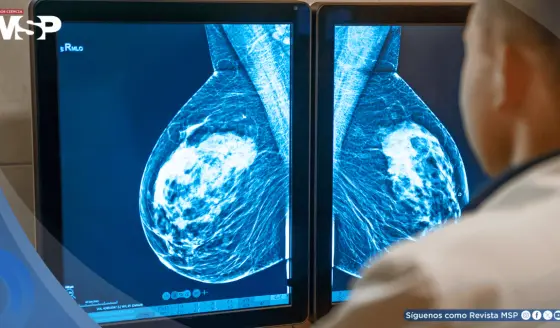

La Genética del Cáncer de Seno en La Familia Puertoriqueña